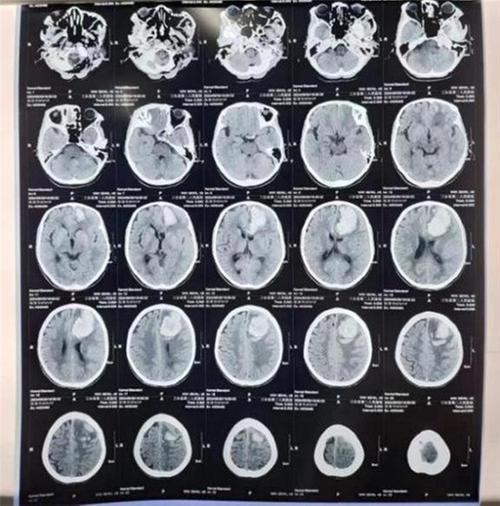

5月30日下午,被家人發(fā)現(xiàn)倒地、昏迷,伴嘔吐、大小便失禁的陳婆婆由急診科外院接回,雙側(cè)瞳孔等大等圓,對(duì)光反射遲鈍,右側(cè)肢體無(wú)反應(yīng),左側(cè)肢體疼痛刺激曲屈活動(dòng)。經(jīng)CT掃描顯示“左側(cè)額葉腦出血,血腫大小約6.2*3.5cm”,于19點(diǎn)18分緊急入住神經(jīng)外科。

(術(shù)前CT示:左側(cè)額葉腦出血)